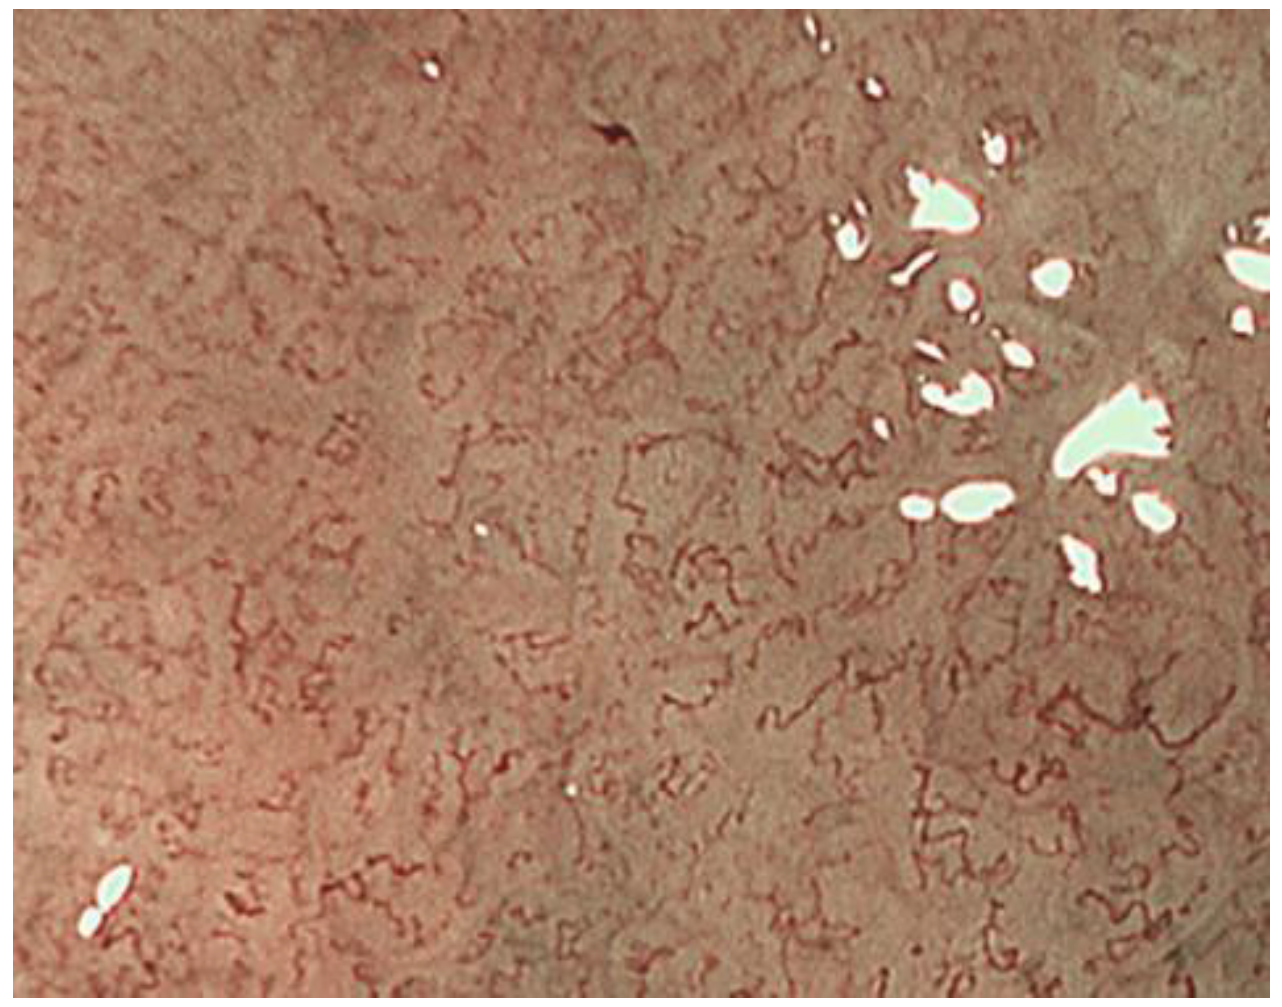

2.1. ME-NBI for Gastric Non-Cancerous Mucosa

- Uedo, N.; Ishihara, R.; Iishi, H.; Yamamoto, S.; Yamamoto, S.; Yamada, T.; Imanaka, K.; Takeuchi, Y.; Higashino, K.; Ishiguro, S.; et al. A new method of diagnosing gastric intestinal metaplasia: Narrow-band imaging with magnifying endoscopy. Endoscopy 2006, 38, 819–824. [Google Scholar] [CrossRef] [PubMed]